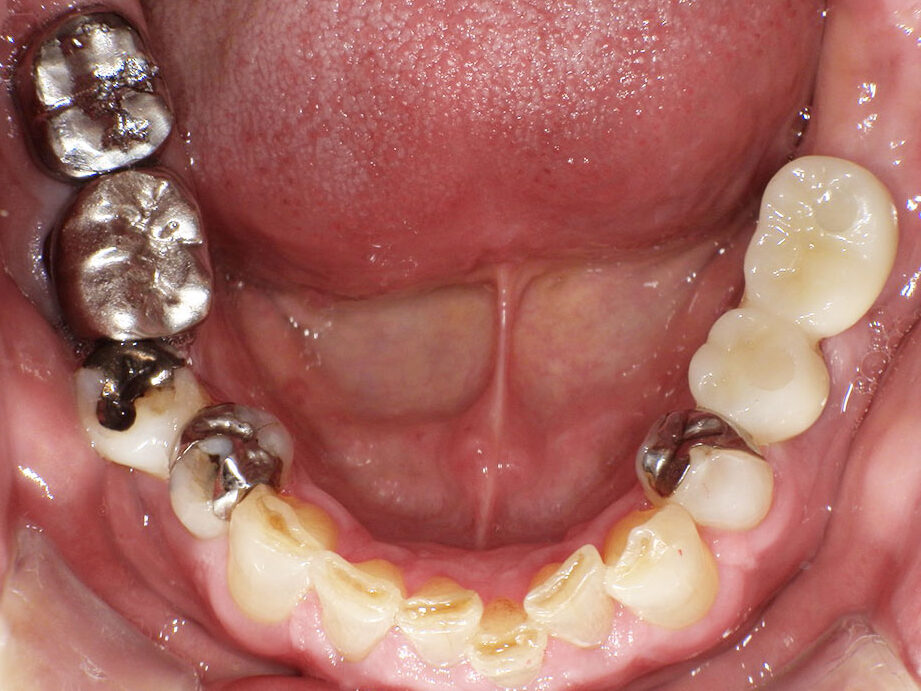

上部構造を装着した写真です。無調整で装着できました。